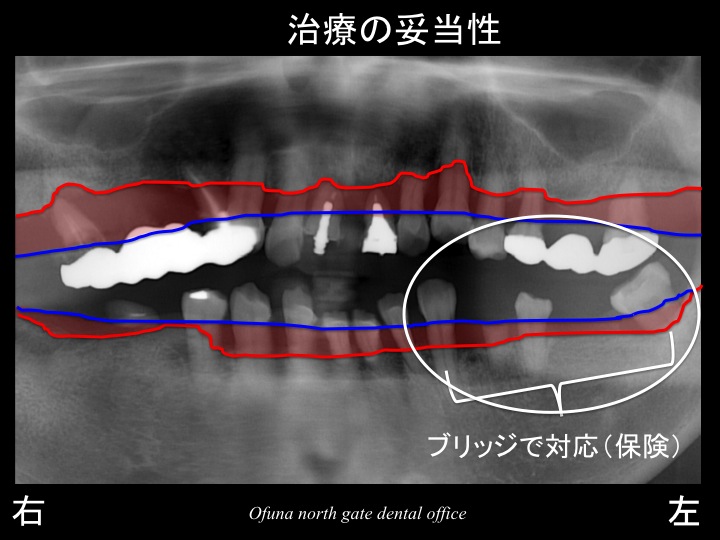

次に下顎左側です。

今回の治療計画では、欠損部周囲の歯を削り、ブリッジという治療方針になりました。

しかし、理想的には、ブリッジではない方が良いでしょう。

下顎左側の奥歯の治療方法としては、

1.ブリッジ

2.義歯(入れ歯)

3.インプラント

になります。

患者様は、取り外し式の義歯は嫌であったため、

ブリッジ もしくは インプラント となります。

理想的にはインプラント治療が良いでしょう。

この理由として、歯を削ることがないからです。

しかし、インプラント治療の場合、費用の問題がどうしてもあります。

今回、右側 や 上顎前歯部 にもインプラント治療を予定しています。

さらに下顎左側までインプラント治療となると これは大変です。

今回の治療で最優先となる治療は、右側です。

右側の奥歯できちんと噛むことが可能となることが

将来的に口腔内を維持するために重要なことなのです。

さまざまなことを考えた結果、下顎左側の奥歯はブリッジで対応することにしました。

また、このブリッジも治療費を抑えることを考え、保険のブリッジにしました。

ブリッジは、残っている歯の数によって違いますが、

ほとんどのケースで保険が適応されます。

ただし、材質は限定されます。(保険で セラミック 等は使用できません)

下顎左側のブリッジの治療費は、約25.000円程度です。